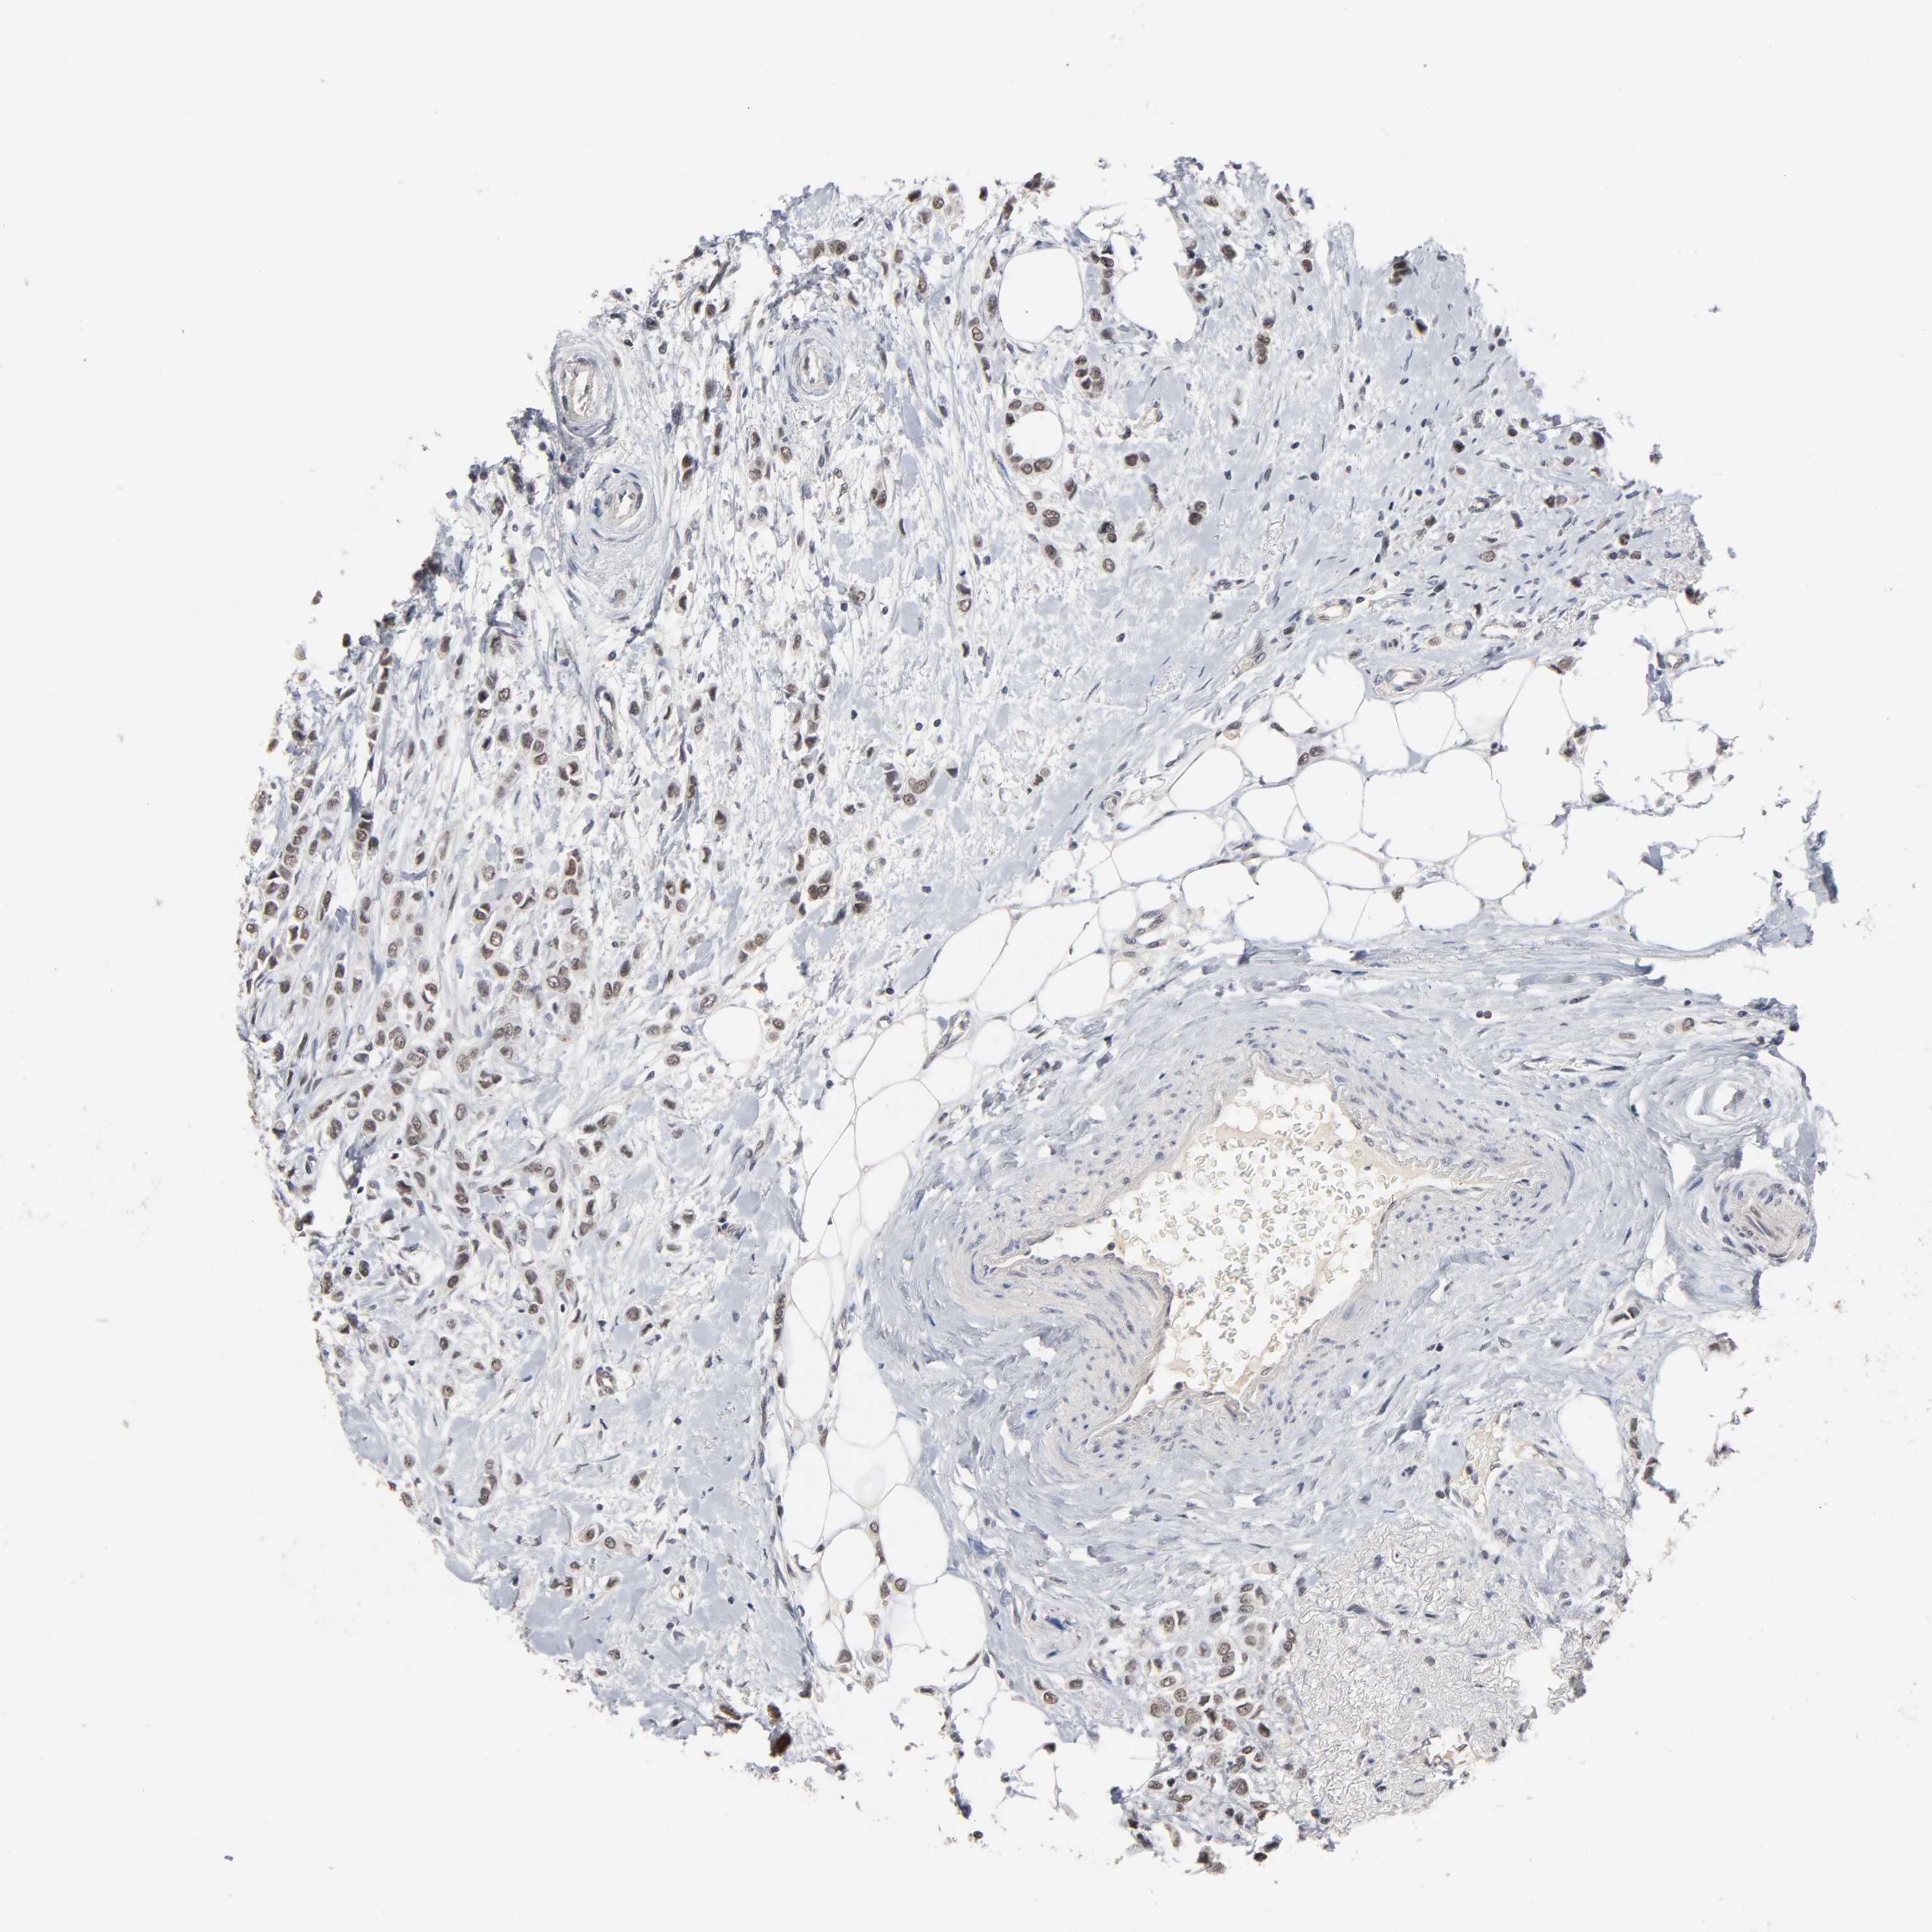

CANCER BREAST CANCER Show tissue menu

BRCA TCGA BRCA VALIDATION PROTEIN EXPRESSION